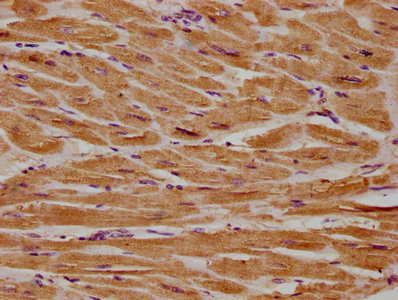

IHC image of CSB-PA860321LA01HU diluted at 1:300 and staining in paraffin-embedded human heart tissue performed on a Leica BondTM system. After dewaxing and hydration, antigen retrieval was mediated by high pressure in a citrate buffer (pH 6.0). Section was blocked with 10% normal goat serum 30min at RT. Then primary antibody (1% BSA) was incubated at 4°C overnight. The primary is detected by a biotinylated secondary antibody and visualized using an HRP conjugated SP system.